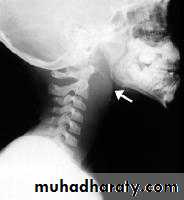

Lateral X-ray of the neck, which shows increase in prevertebral soft tissue shadow or an air-fluid level.

Acute Retropharyngeal Abscess

Lateral X-ray of the neck shows evidence of bone destruction and loss of the normal curvature of the cervical spine.